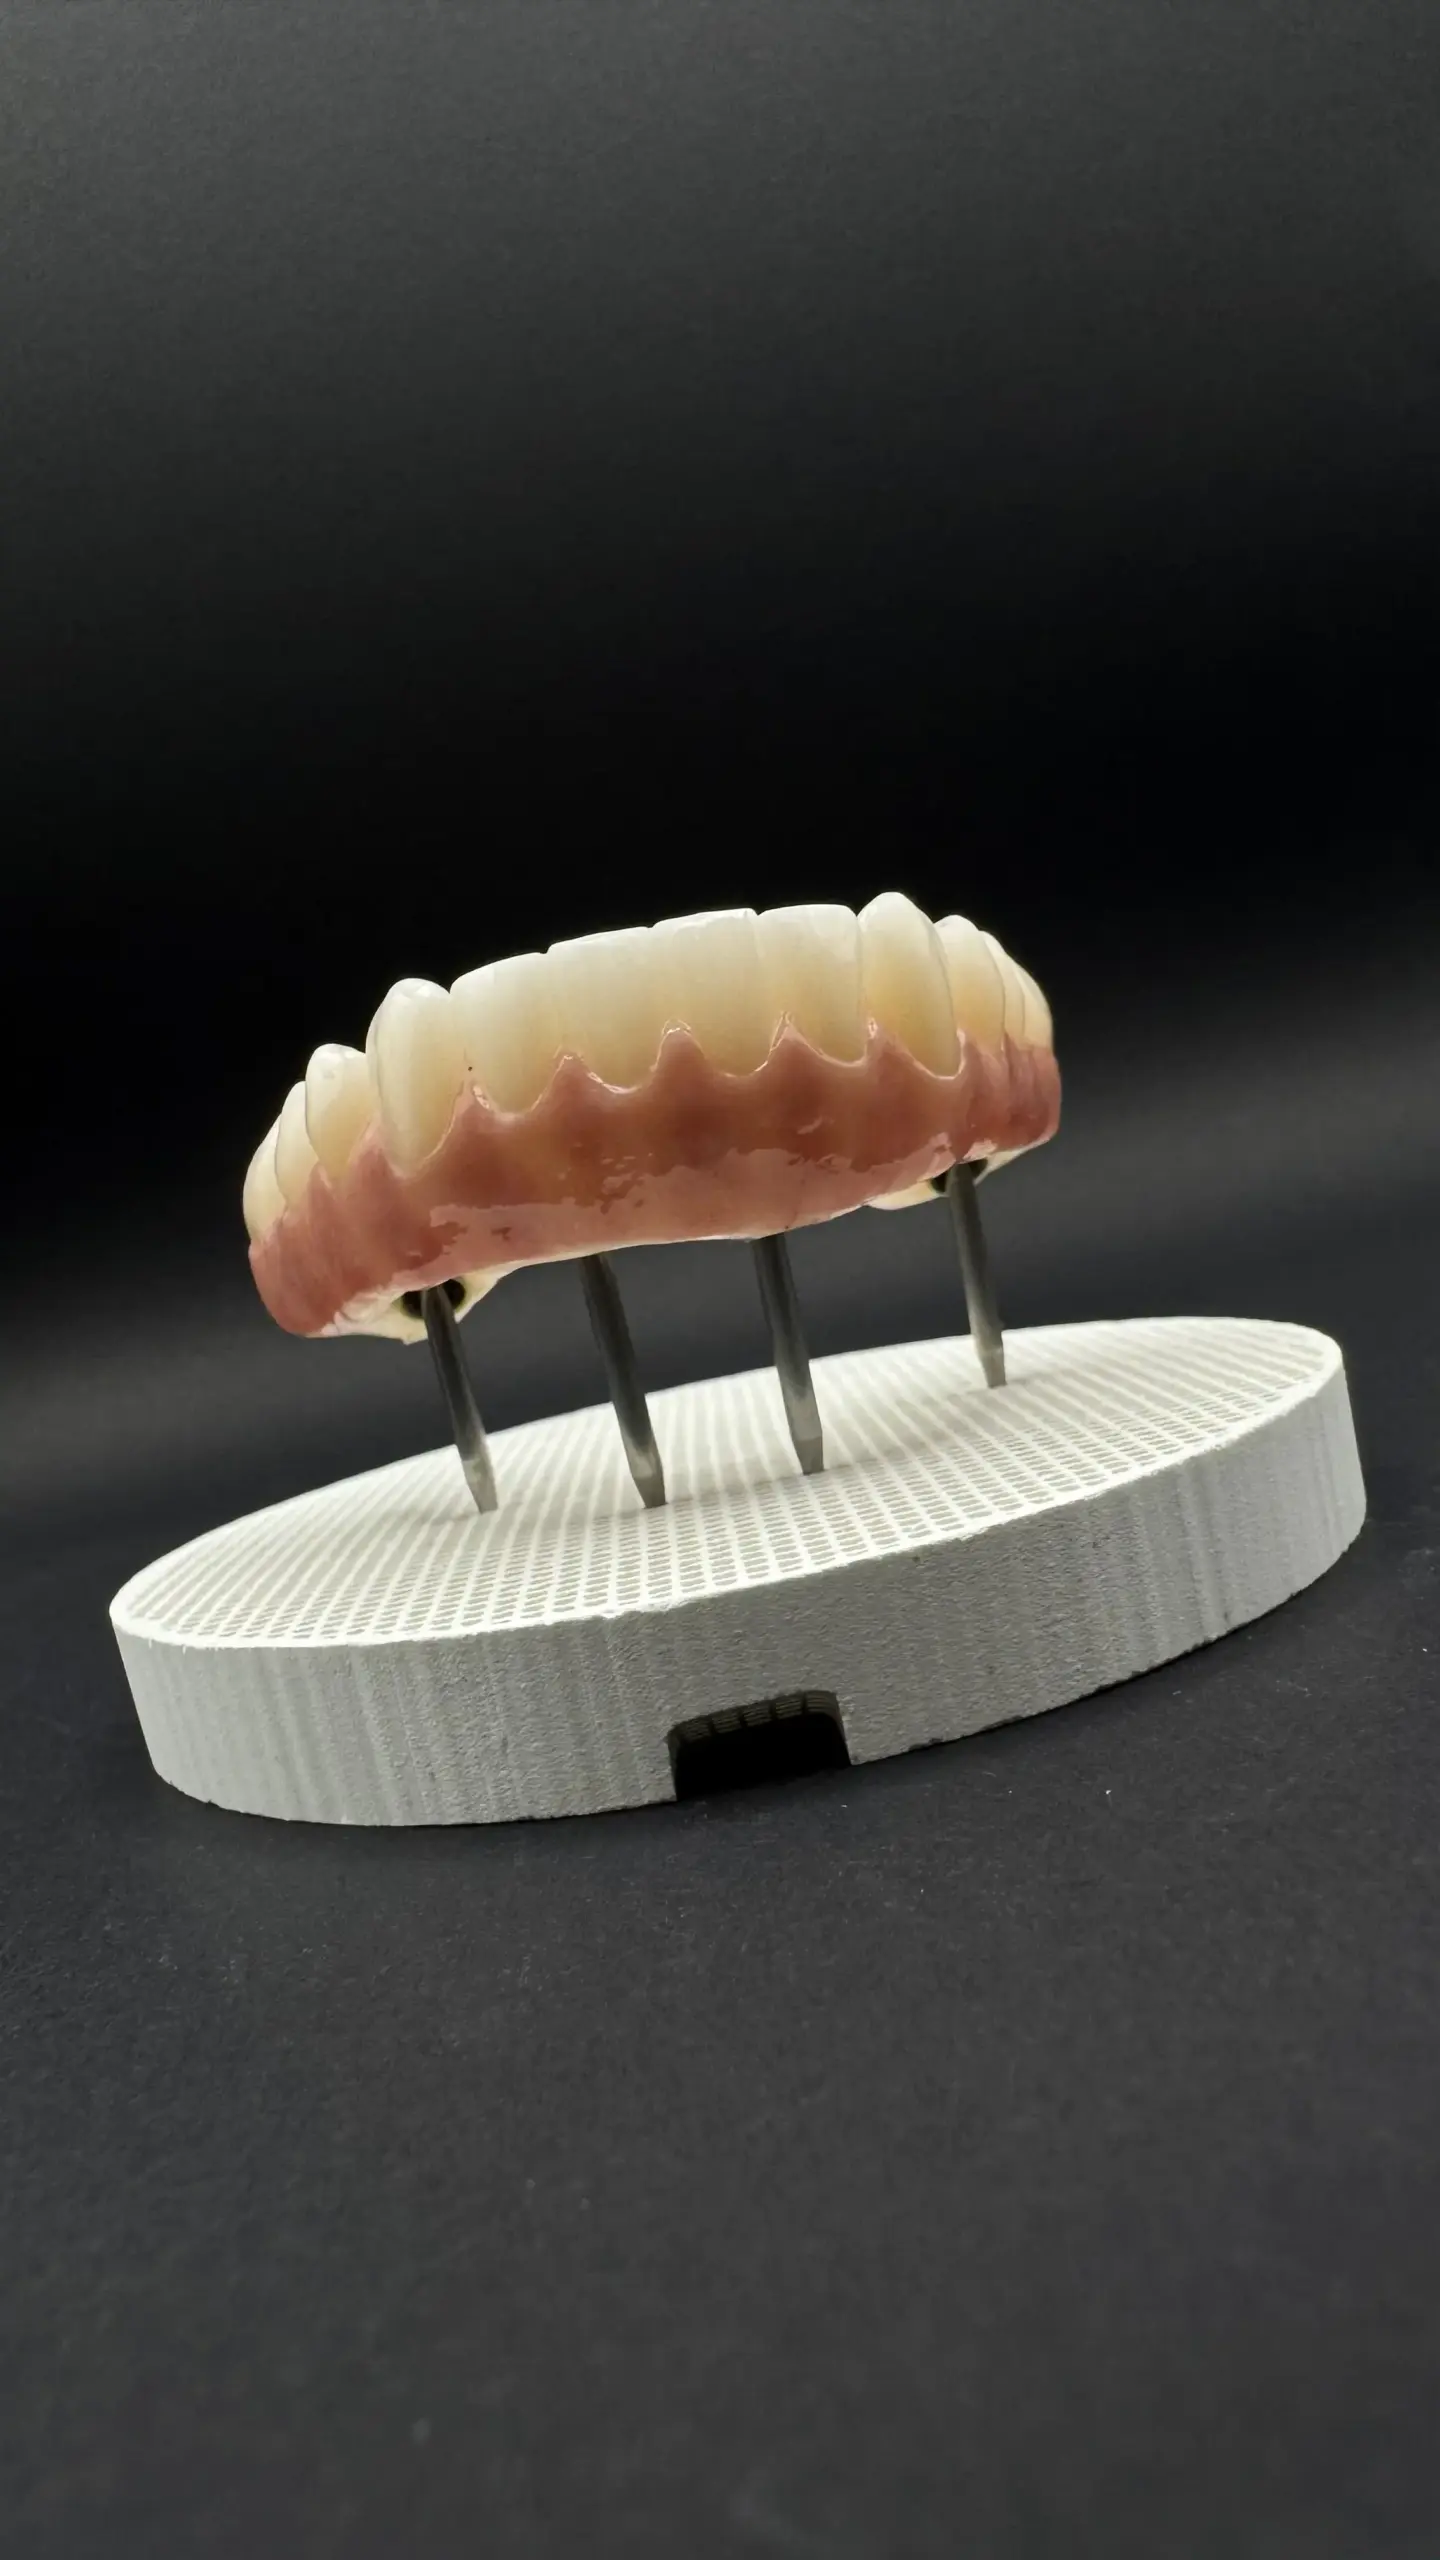

Gama completa

de produtos dentários

Soluções inovadoras e fiáveis para cada etapa da medicina dentária.

PMMA